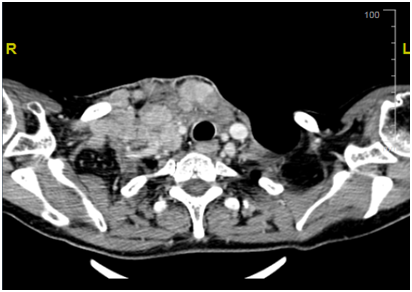

Our patient is a 55yrs. old female with long standing history of Goitre. She underwent total thyroidectomy after confirming Papillary Thyroid cancer on FNA at presentation with slowly progressing neck mass over a course of 1yr. Initial TNM stage showed a T3 N1 M0 Papillary thyroid tumour with extra capsular extension. She proceeded to have radio iodine ablation in May 2016 with 5000Mbq which showed uptake in thyroid bed and Rt neck nodes at level 2. She was then maintained on TSH suppressive dose of thyroxine. Unfortunately, she suffered a relapse in the neck with neck nodes 3 months later i.e. in august 2016 and proceeded to have neck clearance. Again nodes in the RT neck were noted along with extra capsular extension. Pathology, however, showed anaplastic thyroid cancer. Within 6 weeks from her second surgery she came back with rapidly progressing bilateral lower neck nodes. She had a CT which confirmed the recurrence with no distal metastasis. Her recurrence, now second after initial surgery, was deemed inoperable due to the tumour being wrapped around the carotid artery. She proceeded with External Beam Radiotherapy for local control. She progressed on radiotherapy within 2weeks of the start of treatment. This was confirmed on repeat CT scan. No distal metastasis was detectable. Unsurprisingly patient’s thyroglobulin levels were never very high (max level of 20.6). Subsequent levels were within normal limits with no detectable Anti Thyroglobulin Antibody. At this point patient was started on 24mg of Lenvatinib. On her next follow up after 2weeks patient had a complete clinical resolution of her neck nodes and a subcutaneous suprasternal mass as seen previously showed considerable shrinkage. Patient remained troubled with grade 2 fatigue and anorexia but nothing else. At her next appointmentafter2 weeks she had complete disappearance of her disease so much so that a crater was left in suprasternal area i.e. site of her previous subcutaneous tumour extension. Due to persistent fatigue and anorexia dose of Lenvatinib was reduced to 14mg which she is tolerating well. She had a CT at 6weeks which confirmed complete resolution of her disease and no metastasis. She has recently undergone debridement of the lower anterior neck wound and no disease has been detected on biopsy. She awaits her next staging CT in near future (Figure 1).